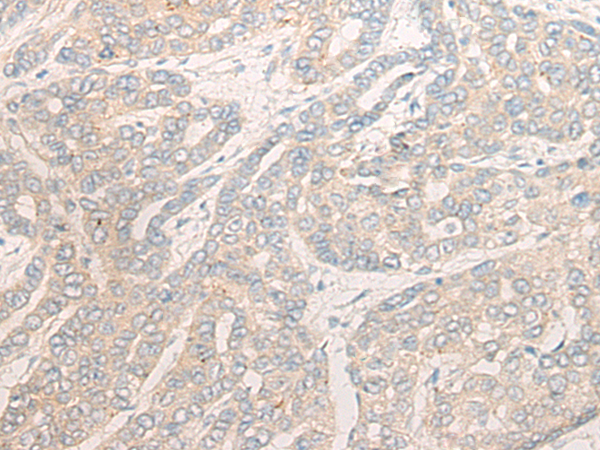

分类: 科研抗体货号: P13262别名: DMN; SYN应用: IHC反应种属: Human